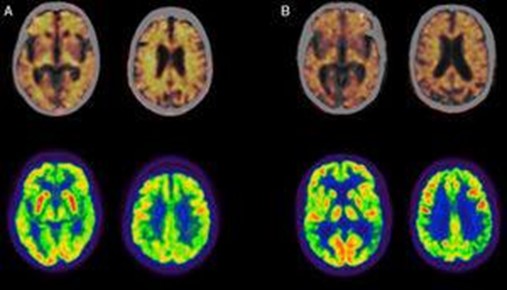

18 F-Fluorodeoxyglucose PET showing variations in Alzheimer and Dementia

PET scan indicating changes in brain glucose metabolism (shown in red and yellow). More prominent in AD indicated by brain tissue with diminished metabolic activity.

FDG-PET study with late-onset (upper) vs. early-onset (lower) Alzheimer Disease